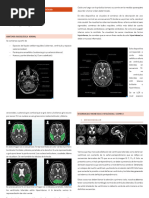

Fig. 1: Escala ARWMC (Age-Related White Matter Changes) para la valoración de

imágenes puntiformes de la sustancia blanca por tomografía computarizada y resonancia

magnética.